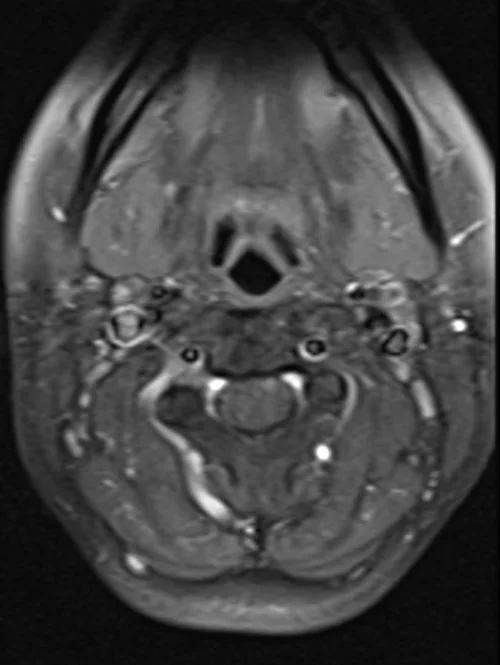

MRI cervical spine T1 FS axial images